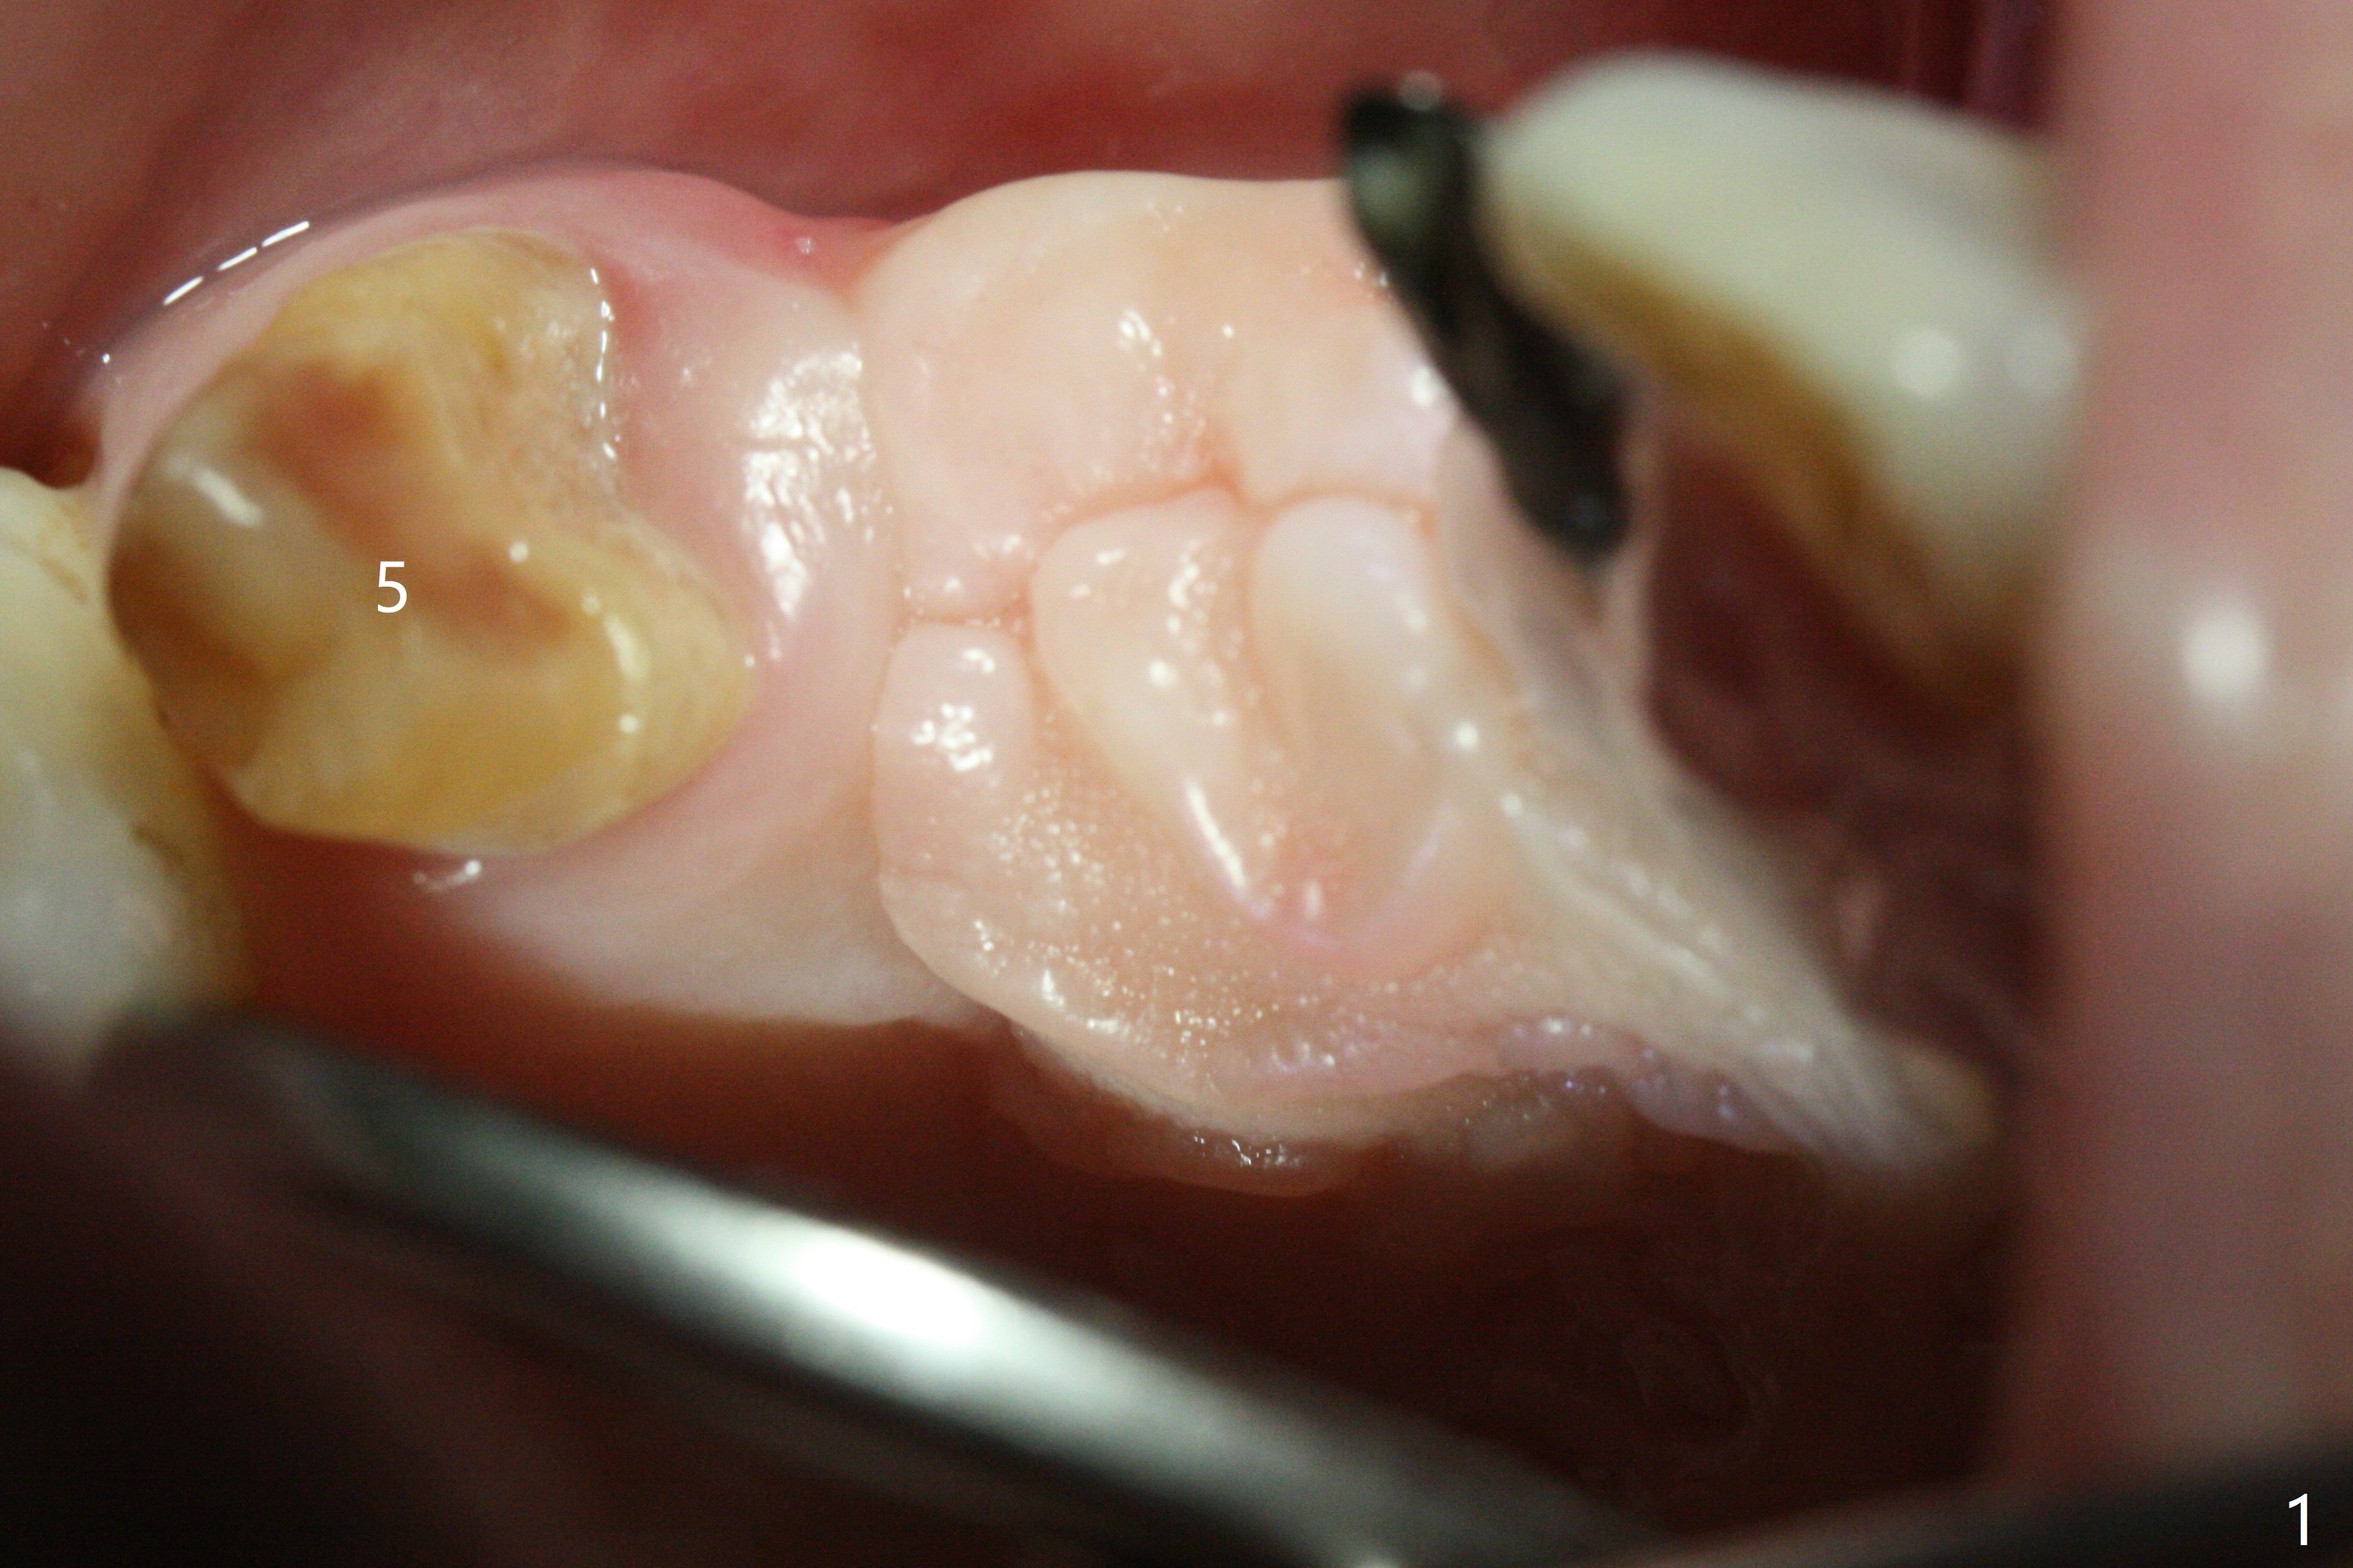

A 51-year-old woman lost the teeth #6 and 7 due to odontoma removal ~30 years ago. The area was restored with a FPD. The latter is removed with immediate implant at #8 8-9 months earlier. Particulate bone graft does not repair the bone deficiency at #6, 7 (Fig.2,3), although the soft tissue looks bulky (Fig.1). It appears that the palatal defect also needs a piece of bone block to fill in (Fig.4). The block will be harvested from the chin (Fig.5,6). If the block graft turns out to be impracticable, the periodontally compromised tooth #5 (bone loss, Fig.2,3,7) will be extracted for immediate implant. Initial osteotomy will be established in the palatal socket (Fig.8,9). Either a 2- (Fig.10) or 1- (Fig.11) piece implant will be placed. After wound healing, impression will be taken for a lab-fabricated provisional FPD.